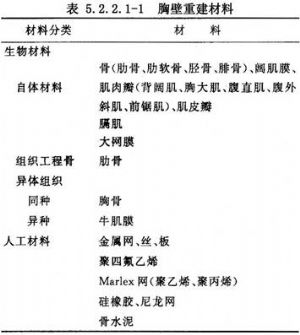

胸壁重建材料較多,有生物材料及人工材料兩大類。見表5.2.2.1-1。